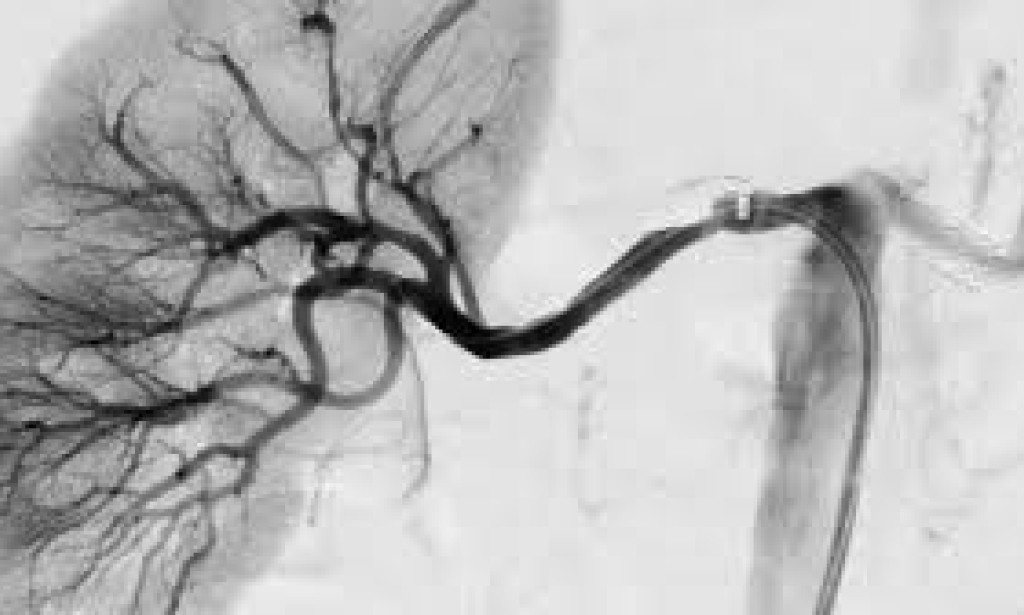

Hypertension, or high blood pressure, is another leading cause of kidney failure. When blood pressure remains consistently high, it can damage the blood vessels in the kidneys, reducing their ability to filter waste and maintain fluid balance. This condition, called hypertensive nephropathy, can lead to kidney failure over time.

The kidneys are responsible for regulating blood pressure through a complex system involving the kidneys' filtration processes. When kidney function declines, this regulation becomes disrupted, leading to further increases in blood pressure, creating a vicious cycle. As the kidneys become less effective at filtering blood, more toxins accumulate in the body, contributing to the progression of kidney failure.

Dr. David Miller, a cardiologist, notes, "Chronic high blood pressure can cause the arteries in the kidneys to narrow, weaken, or harden, making it difficult for the kidneys to effectively filter waste. This ultimately leads to kidney damage."